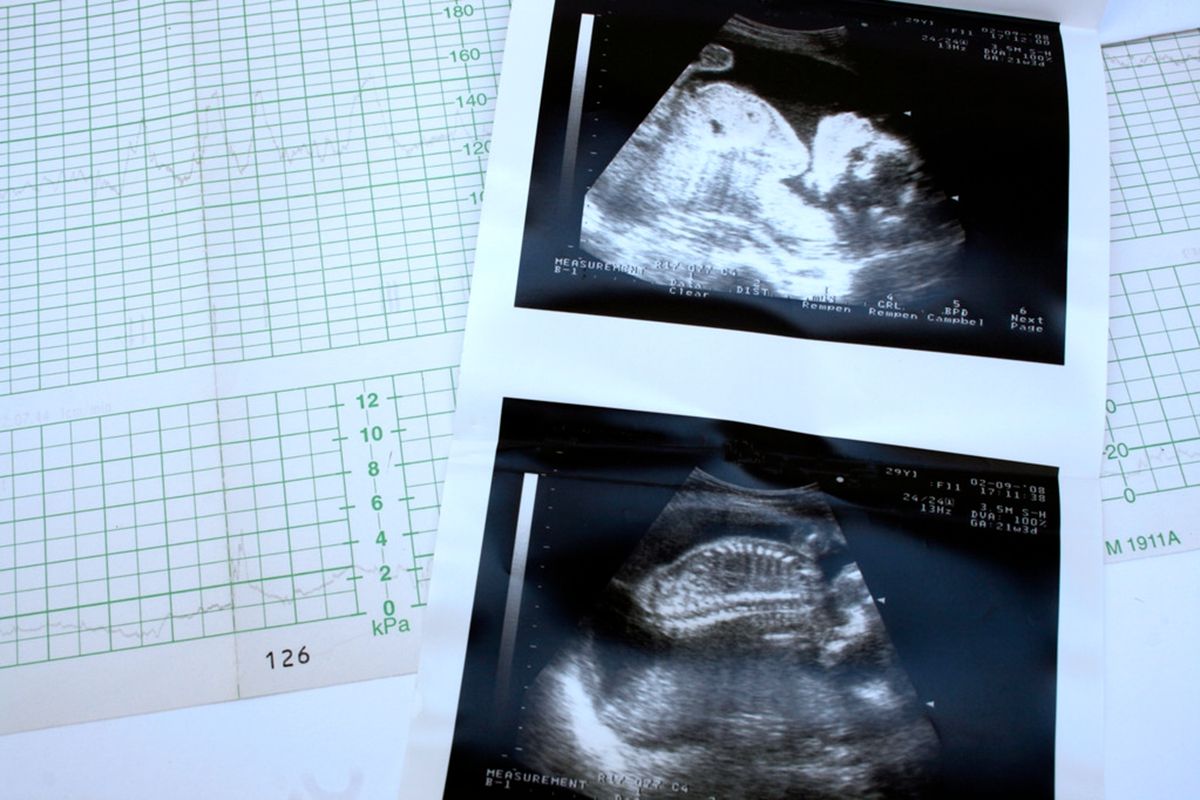

原来还有这一招,小珂回到家就翻阅起自己的孕检报告单,但是报告单上的心率值却让她傻眼了。

小珂发现,从几次孕检的数据来看,胎儿的心率有几次是低于140次每分钟,有几次是高于这个数的。

小珂发现在自己孕晚期几次B超检查报告中,胎儿的心率都是不同的。这样的情况非常正常,孕妈大可不必担心。